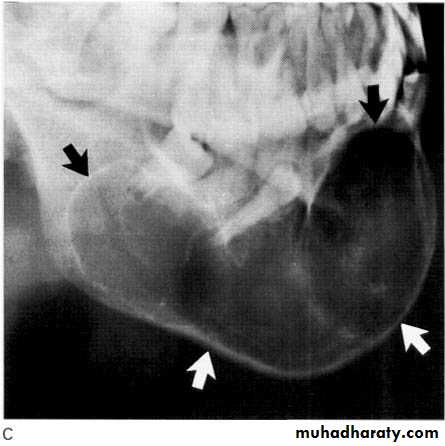

Dentigerous (follicular) cyst

This cyst develops from the remnants of the reduced enamel epithelium after the tooth has formed.

Site: Associated with the crown of an unerupted e.g. 3|3 and 8|8.

Size: Very variable, cyst suspected if follicular space exceeds 3 mm but may grow to several centimeters in diameter and extend up into the ramus.

Shape: — Round or oval, typically enveloping the crown symmetrically

— Monolocular

Outline: — Smooth

— Well defined

— Often well corticated.

• Radiodensity: Uniformly radiolucent